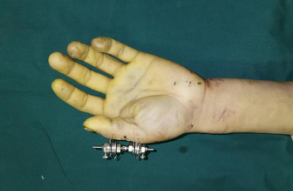

术后即刻

术前工作准备完毕,齐伟亚、刘桂谦手术团队为张师傅进行了进行了关节镜辅助下左桡骨远端骨折复位内固定+滑膜清扫,机器人导航下左腕钩状骨骨折复位内固定,左手第1掌骨骨折复位内固定,左拇指近节指骨骨折外固定架外固定,虽然手术时间稍长,但是手术很顺利,术后张师傅恢复良好,张师傅一家称赞齐主任的医技好,而且从患者的角度出发,不让患者多花一分钱。